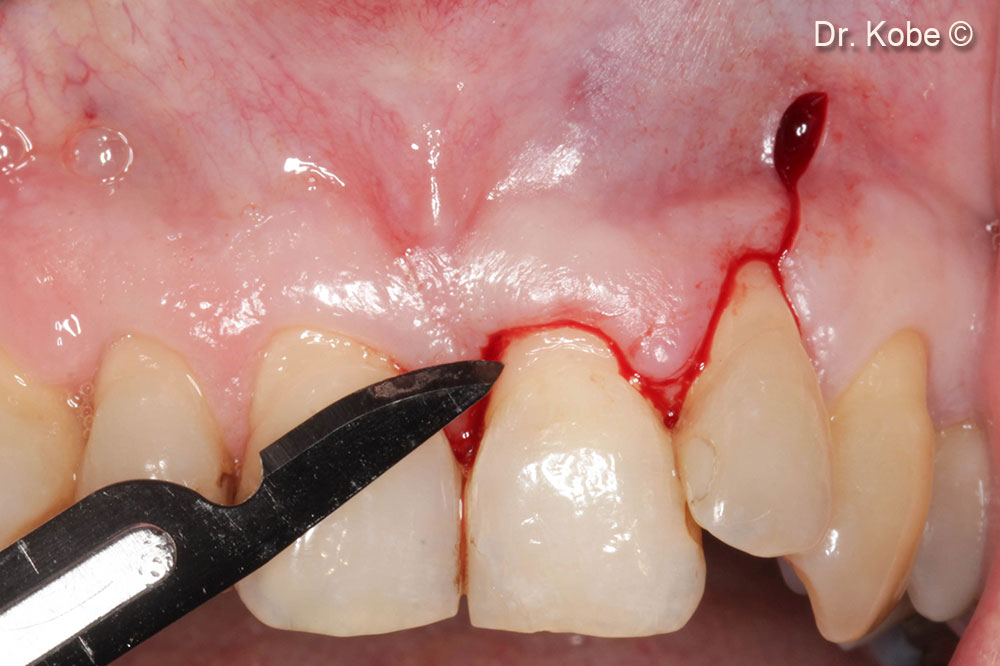

3. Horizontal incision at the adjacent tooth